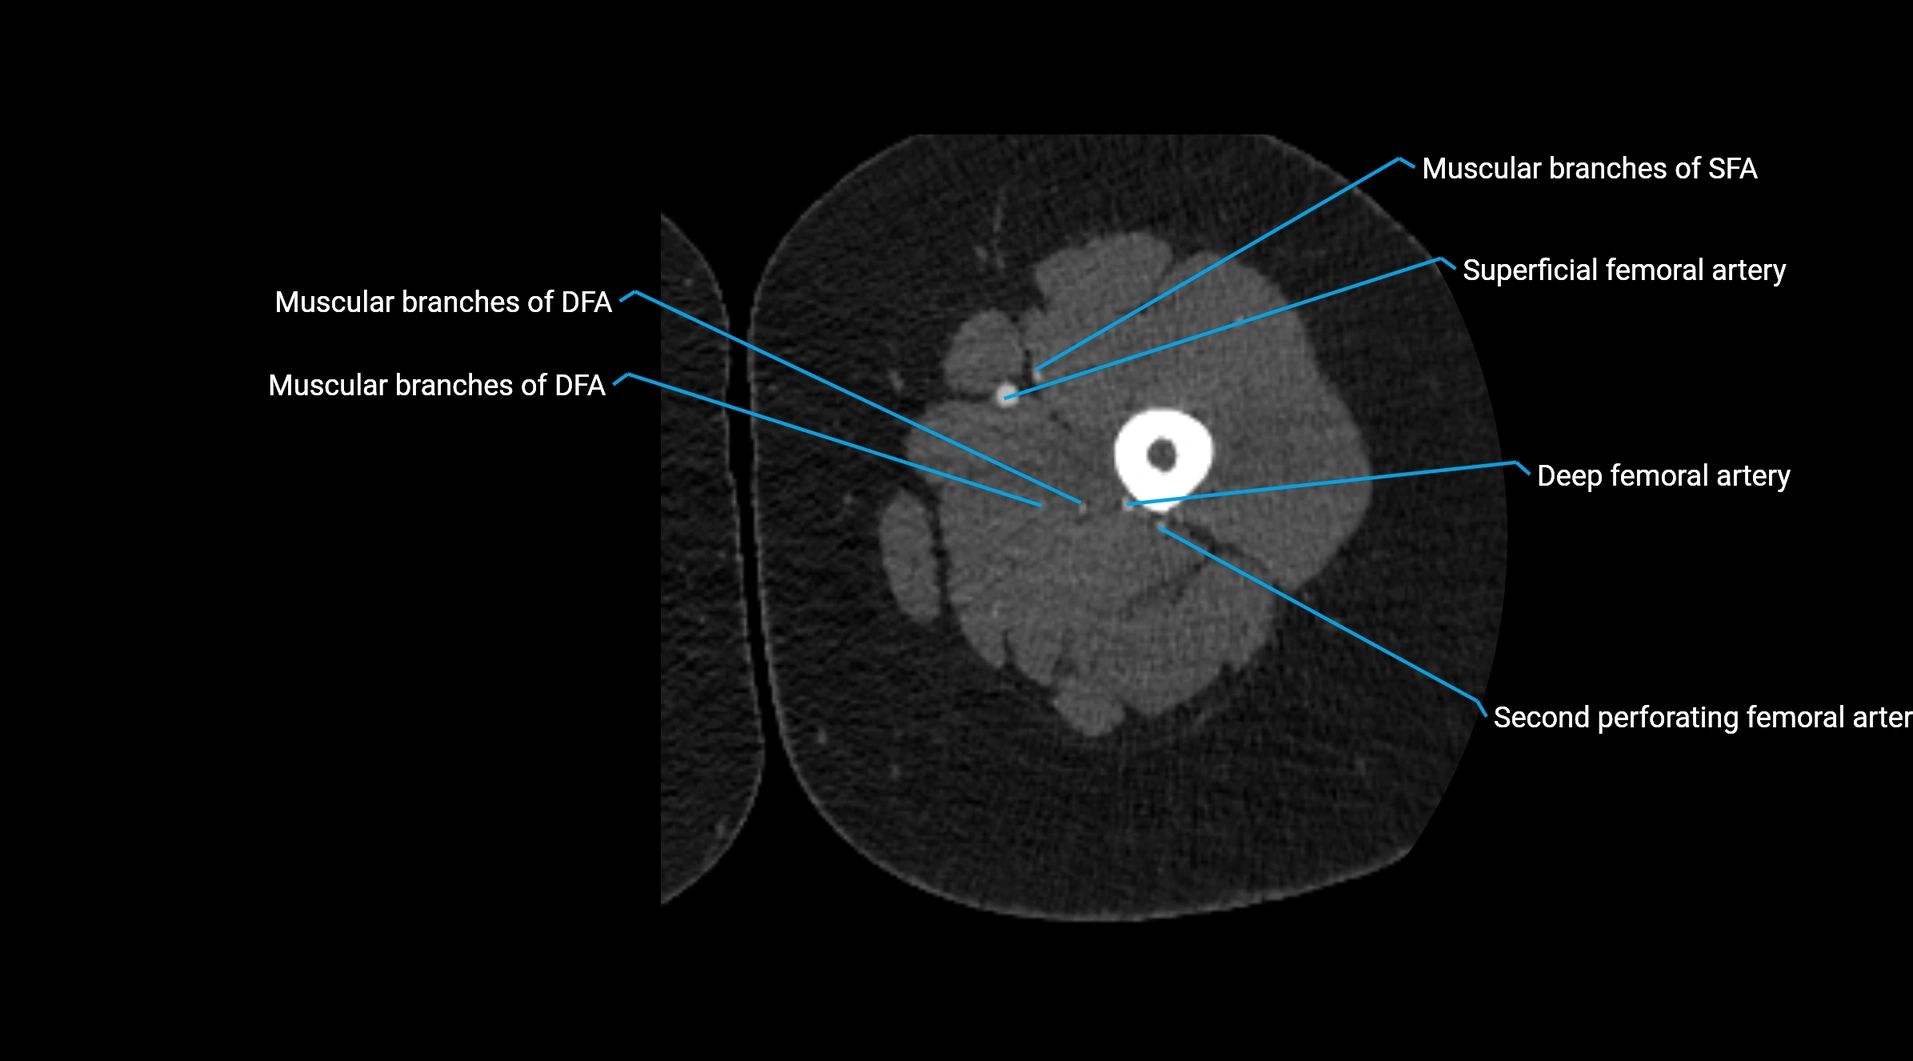

CT images

image